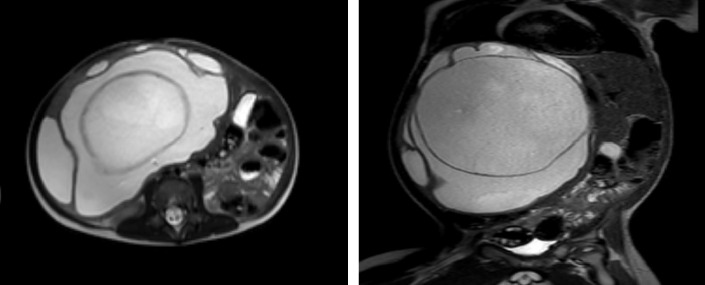

Benign liver tumors are infrequently observed in the pediatric age group, with an incidence reported at 0.7 per million population annually. Among these tumors, mesenchymal hamartoma constitutes 18%-29%. Imaging studies commonly reveal a well-marginated, solitary mass, often measuring up to 30 cm. The mass, primarily located in the right liver lobe (75% of cases), may exhibit a pedunculated structure. We present a case of a 1-year-and-9-month-old boy diagnosed with hepatic mesenchymal hamartoma. A contrast-enhanced computed tomography of the abdomen and magnetic resonance imaging (MRI) were performed and demonstrated a large multiloculated septated liver lesion measuring approximately 13.6 × 17.7 cm, demonstrating multiple partially thickened internal septations. The procedure was done for the patient in the form of an extended right hepatectomy with segment 4A and cholecystectomy.